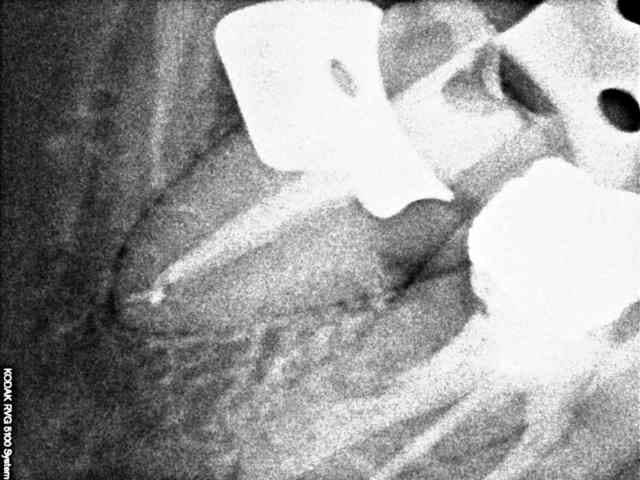

Un patient se présente avec une lésion carieuse importante sur 47. Je fait une rétroalvéolaire. La forme de l'endodonte m'interpelle, je curete et ne fait pas d'effraction pulpaire, donc je met un CVI. Le patient fait une pulpite, je fait le traitement, j'ai trouvé un très gros canal distal que je pensais unique, puis un tout petit mésial bien centré dans le sens linguo vestibulaire.

Avez vous déjà rencontré ce type de dent.

Ai-je tout obturé?

PS: J'ai mis la radio de la dent controlatérale un confrère n'avait visiblement pas mieux compris l'anatomie canalaire.